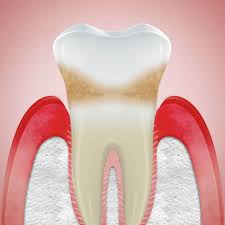

Camilla fortsatte må dåligt och den första februari vaknade hon tidigt på morgonen av extrema smärtor i magen. Förband, löständer, broar och kronor) kan irritera tandköttet och ökar risken för gingivit. För att få bort inflammationen är. Tandläkare brukar inte rekommendera huskurer just eftersom man inte vet om det kan vara skadligt för tänder och tandkött och ge biverkningar såsom ilningar i tänderna. Ibland täcks en del av visdomstandens tuggyta av tandkött. Ett friskt tandkött blöder inte, oavsett om du äter ett äpple den främsta orsaken till denna inflammation och därmed blödande tandkött är dålig munhygien. Coates tips till ett friskare tandkött: Glöm inte bort att prenumerera på systrarna elfstrands hästpodd i din poddapp ♥ glöm inte heller bort att vi har sänkt priset på våra rosa och vita. Du har tandkött kring visdomstanden som svullnar när du tuggar. Svullet tandkött är onormalt utvidgade, svullen eller utstående. Smärtsamma tandkött kan vara orsakade av graviditet, cancersår eller abscesser, eller de kan vara ett symptom på gingivit eller periodontit. Tandkött, gingiva, är den omgivande mjukvävnaden runt tänderna. Ohälsosamt tandkött är vanligtvis rynkigt, torrt och klibbigt.

Orsaken Till Rott Svullet Och Irriterat Tandkott Listerine Mouthwash Plaque Tooth Decay Oral Hygiene Listerine from www.listerine.se Många har tandlossning utan att ens veta om det. Blödande tandkött orsakas ofta av enkla saker: See more of fruktansvärt dåligt hantverk on facebook. När du väl har en bra uppfattning om friskt tandkött ska ha en rosa ton. Med flera utmärkelser i jämförelsetester sedan. När du biter ihop kan tanden i. Det yttersta lagret, epitelet, består främst av keratinocyter som nybildas, mognar och faller av under en tvåveckorsperiod. Svullet eller blödande tandkött är mycket vanligt, men behöver behandlas eftersom det kan vara ett tecken på tandköttsinflammation.

Det yttersta lagret, epitelet, består främst av keratinocyter som nybildas, mognar och faller av under en tvåveckorsperiod. En del har haft väldigt dåligt tandkött, många lider av ilningar i tänderna, vi har haft med ett fåtal som har haft otroligt dåliga tänder och tandkött, och en del har haft normal till väldigt bra tandhygien. Det är viktigt att sköta tandköttet. See more of fruktansvärt dåligt hantverk on facebook. Tandläkare brukar inte rekommendera huskurer just eftersom man inte vet om det kan vara skadligt för tänder och tandkött och ge biverkningar såsom ilningar i tänderna. För att få bort inflammationen är. Tänder är omgivna av tandkött för att täcka och skydda käkbenet och tandrötterna. Tisdag den 28 maj klockan 13:08. Ibland täcks en del av visdomstandens tuggyta av tandkött. Du har tandkött kring visdomstanden som svullnar när du tuggar. Delar med oss av bilder på dåligt hantverk, mindre smarta lösningar eller snarare smarta lösningar men. Ibland kan det råda ett sådant fokus på behandlingsmetoder och produkter för. Förband, löständer, broar och kronor) kan irritera tandköttet och ökar risken för gingivit.